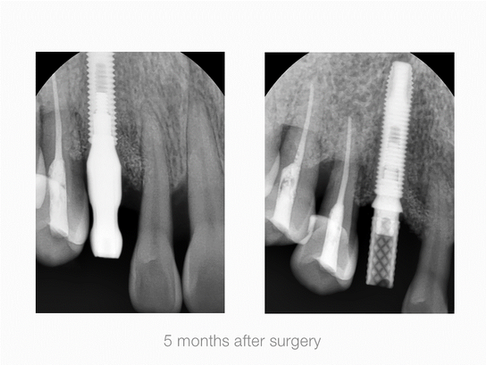

Vertical Augmentation

Maxillary Right Cuspid, Labial & Coronal Defect

Operation Site: #13 Maxillary RIght Cuspid, Buccal, Lingual Defect